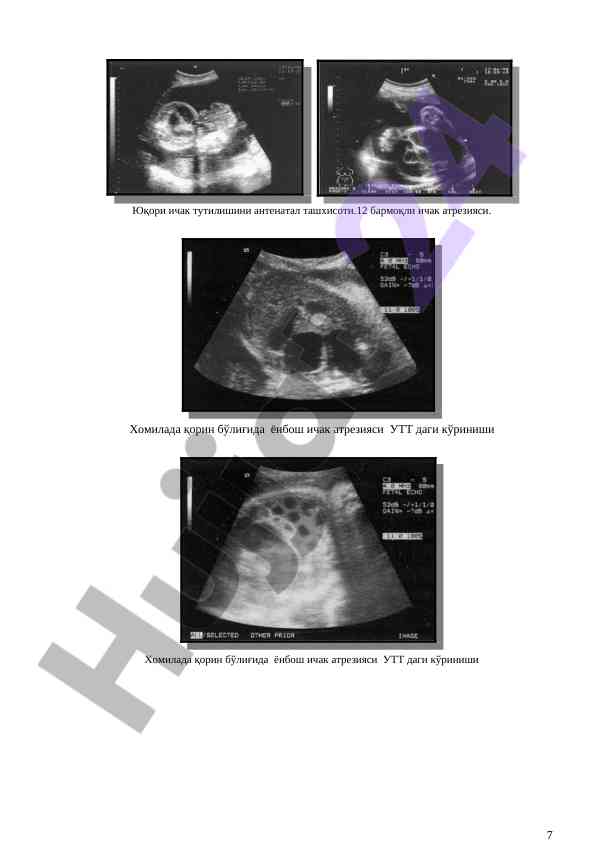

Bolalar uchun tug‘ma nuqsonlar va hirurgik kasalliklar diagnostikasi va davolash taktikalarini o‘rgatishga qaratilgan maqola. Mavzular: zamonaviy yondashuvlar, operativ davolash, endoskopik diagnostika, hamda bolalar jarrohligi.